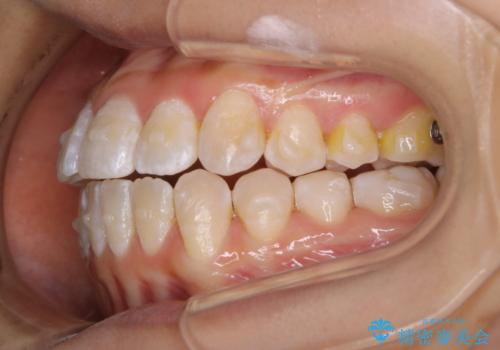

前歯のがたつきとオープンバイト:インビザラインでまとめて治す

- 噛み合わせと、前歯のがたつきが気になるとご相談にいらした方です。インビザラインFULLで綺麗な歯並びと噛み合わせを作ることが出来ました。

オープンバイトの方への治療は、通常抜歯を行いワイヤーによる矯正治療を行うことが多いですが、今回はインビザラインの特性を生かし、非抜歯にて綺麗な歯並びを作ることが出来ました。